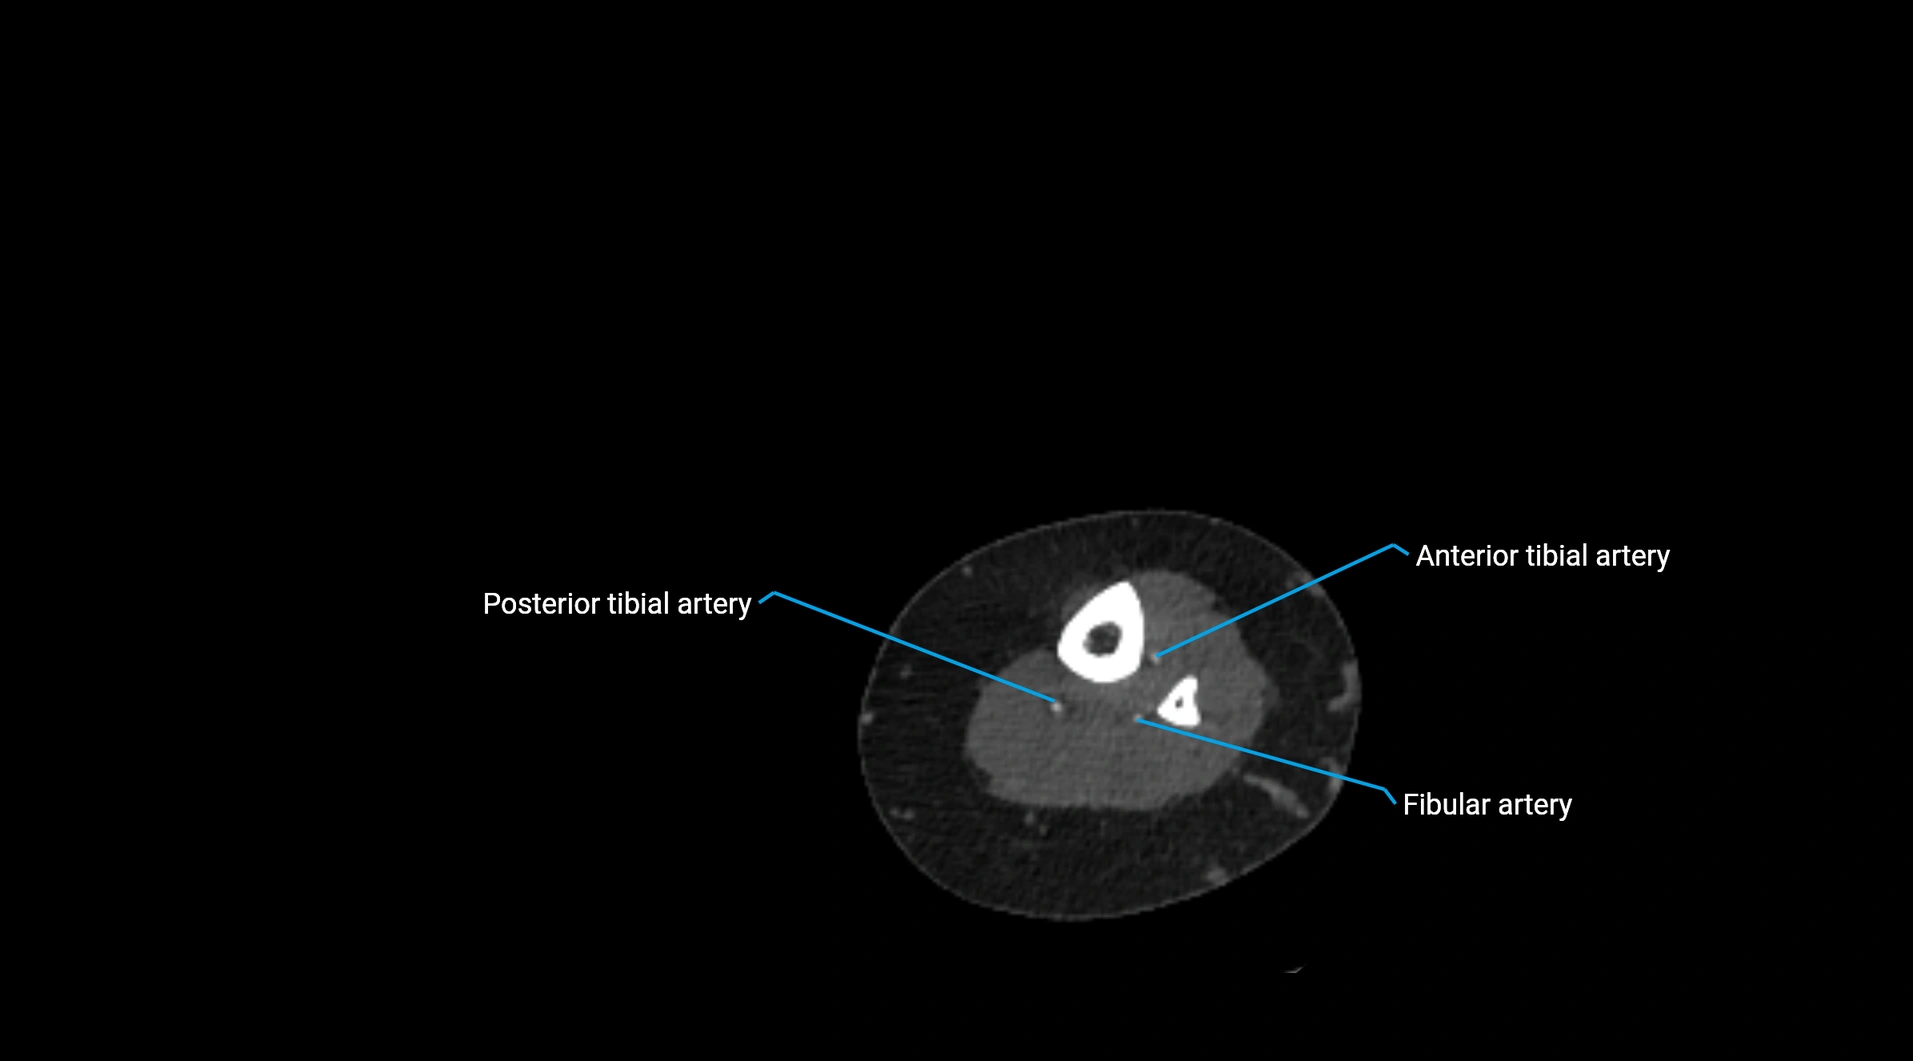

Contrast-enhanced CT (CTA):

• Gold standard for abdominal aortic imaging

• Provides excellent detail of lumen, wall, aneurysm, thrombus, and branch vessels

• Multiplanar and 3D reconstructions help in aneurysm measurement, stent graft planning, and dissection evaluation